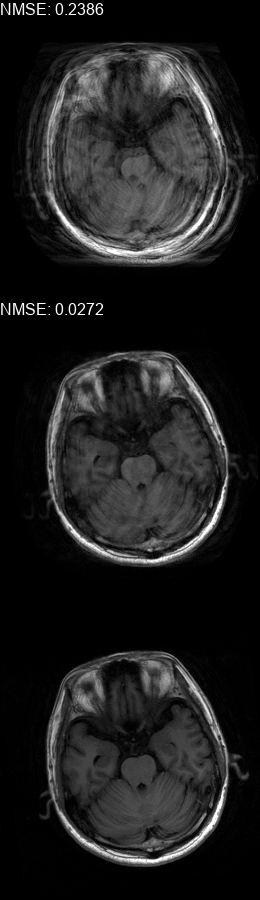

Fig. 5 contains four scan reconstructions from two patient cases. In both cases, the patient was requested to move at a certain time. In order to provide a ground truth for this scenario, another scan was performed using the same protocol for each patient, where the patient was required to hold still. The motion timing information for this case was obtained using the method described in [2] as it requires no additional hardware or changes to the scan protocol. We compare the reconstruction error using the SSIM [17] and the Visual Information Fidelity (VIF) [16] metrics, since a pixelwise comparison is not viable in this case.

Figure 5: Examples of real motion corrupted images together with their motion corrected counterparts. The bottom row shows a corresponding slice from a motion-free acquisition of the same subject. These motion-free images were acquired using an additional scan. The images on the top row are motion-corrupted. Images on the middle row were corrected using our method. (a,b) motion was was detected at t1=96subscript𝑡196t_{1}\!=\!96, (c,d) the motion was detected at t1=112subscript𝑡1112t_{1}\!=\!112. All scans were acquired using 𝒮260subscript𝒮260\mathcal{FS}_{260} presented in Fig. 1b.